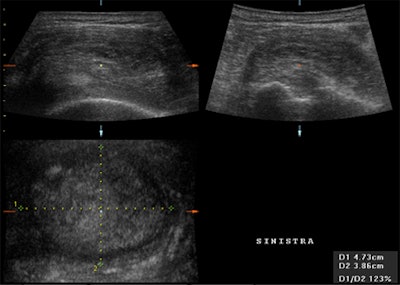

![]() |

| Multiplanar representation of a subscapularis tendon partial tear. All three planes demonstrate an area of an irregular anechoic defect in the upper surface of the tendon (on the bursal side of the rotator cuff) while inferiorly, the tendon remains intact. |